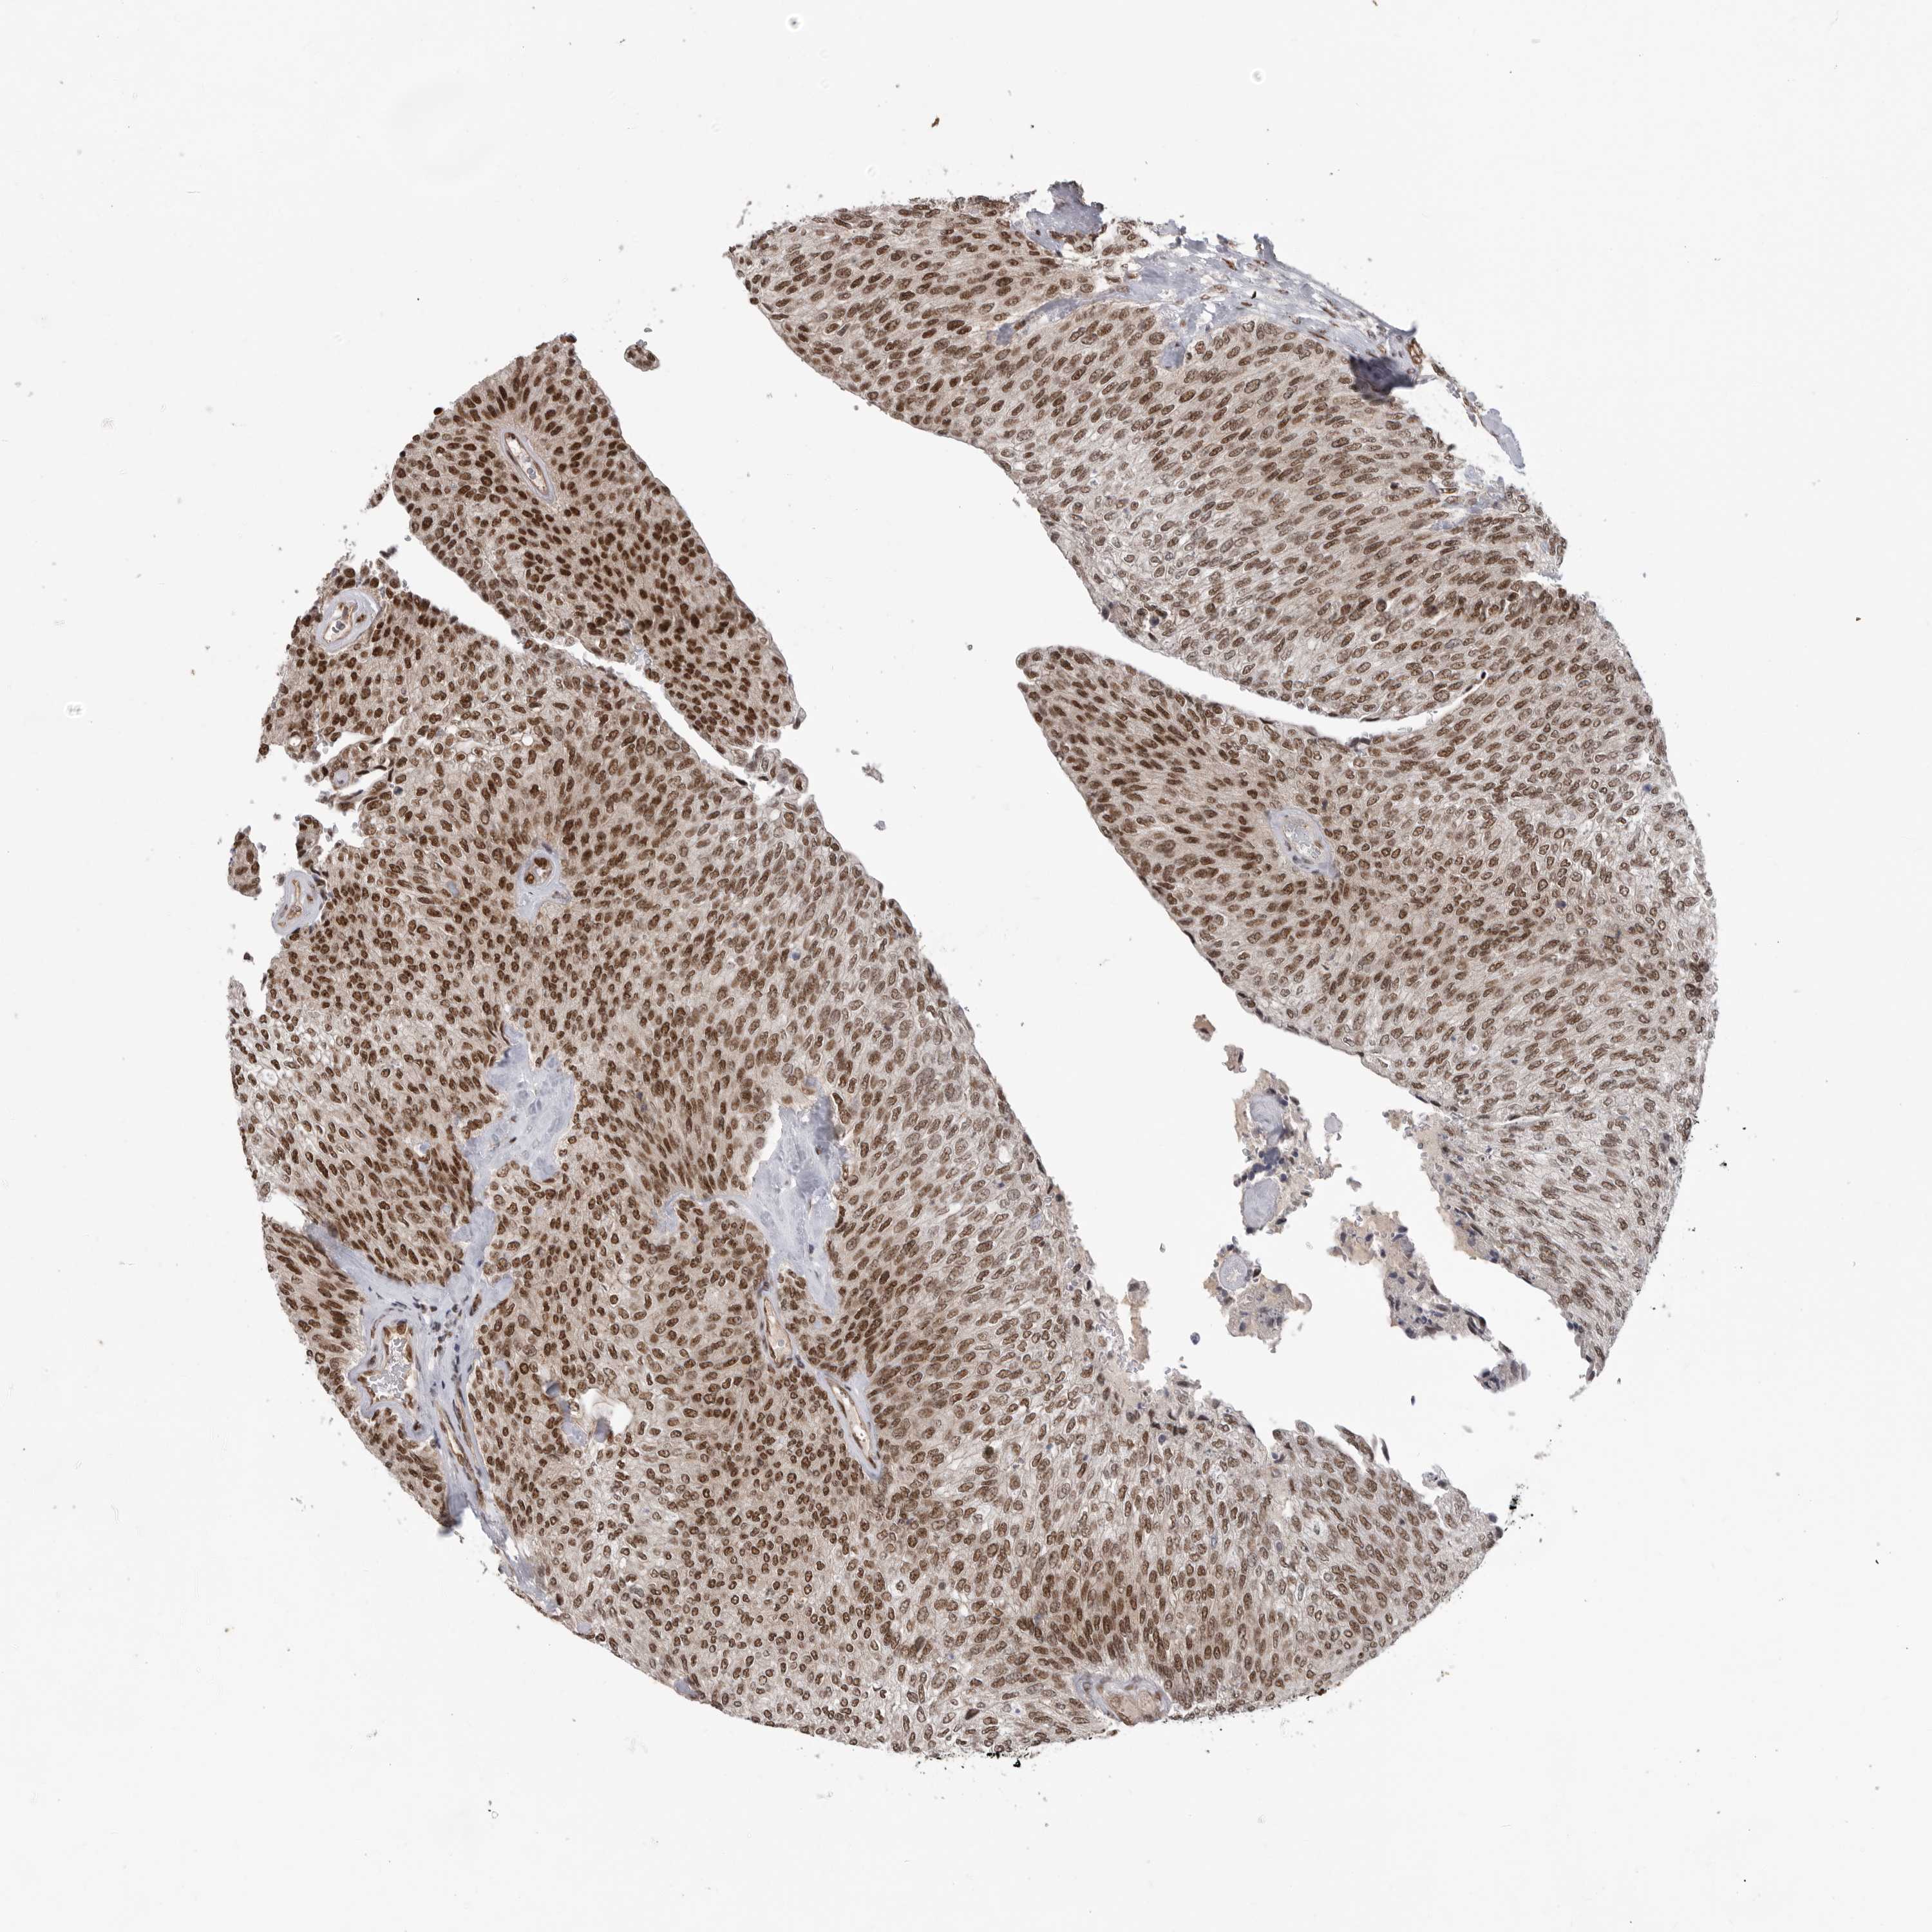

UROTHELIAL CANCER - Protein expressioni

A mouse-over function shows sample information and annotation data. Click on an image to view it in a full screen mode. Samples can be filtered based on level of antibody staining by selecting one or several of the following categories: high, medium, low and not detected. The assay and annotation is described here.

Note that samples used for immunohistochemistry by the Human Protein Atlas do not correspond to samples in the TCGA dataset.

Antibody stainingi

Antibody staining in the annotated cell types in the current human tissue is reported as not detected, low, medium, or high, based on conventional immunohistochemistry profiling in selected tissues. This score is based on the combination of the staining intensity and fraction of stained cells.

Each image is clickable and will lead to virtual microscopy that enables deeper exploration of all samples and also displays staining intensity scores, fraction scores and subcellular localization as well as patient and tissue information for each sample.

Antibody HPA027406

Antibody HPA027417

Antibody HPA027452

Staining

High

Medium

Low

Not detected

Intensity

Strong

Moderate

Weak

Negative

Quantity

>75%

75%-25%

<25%

None

Location

Nuclear

Cytoplasmic/membranous

Cytoplasmic/membranous,nuclear

Urothelial carcinoma, Low grade

Urothelial carcinoma, High grade